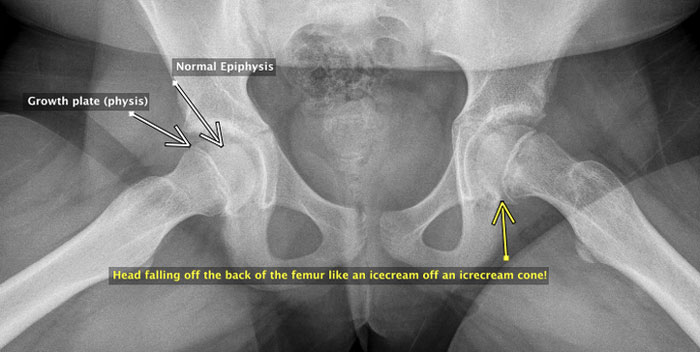

Slipped epiphysis (SUFE, SCFE) is a relatively uncommon childhood condition where the ball of the femur in the hip joint slides off the back of the femur to a small or large extent. The problem occurs in the growth plate of the hip (physis) the head part is the epi-physis.

It causes pain in the leg – it can be over the knee, but might be in the thigh or groin. If the slip is severe, the leg points outwards. If acute, the pain can be severe and the child unable to walk. If more subtle and subacute, the limp might be the most obvious feature.

If the initial concern is the knee, and health practitioner finds nothing wrong with the knee, then x-ray of both hips is required to be sure the cause of the problem isn’t a slipped epiphysis.

This case demonstrates on XR the left hip in a “frog leg lateral” (right side your screen) demonstrated the subtle signs of a slipped epiphysis.